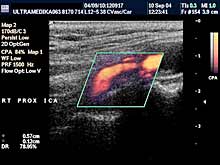

A) Krvni sudovi vrata

Vrsta i sadržaj pregleda:

- Pregled velikih krvnih sudova vrata CD i CPA

modom (obavezno karotidnih i vertebralnih arterija celim tokom).

Pregled podrazumeva procenu ukupne debljine krvnih sudova (indirektna

procena koronarne bolesti), procenu stepena suženja, karakteristika aterosklerotičnog plaka, procena hemodinamike i postavljanje

indikacija za operativno lečenje.

Primenjena tehnika:

- Sono CT,

- XRes,

- 2D Broad band,

- Broad band - CD,

- CPA ,

- CPD.

Preporučeni pregledi:

- nakon 45. godine starosti,

- obavezno ako postoje

faktori rizika

(hipertenzija, pušenje, stres, poremećaj nivoa masti u

krvi, kod sumnje da postoji koronarna bolest),

- kontrola na 6-12

meseci.